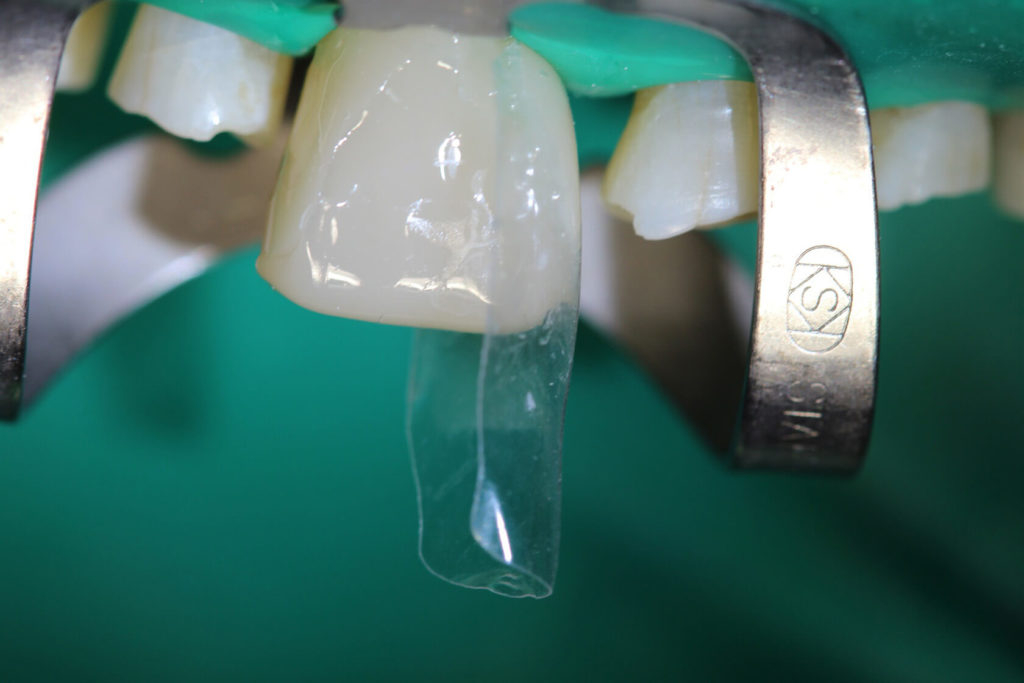

This 50 year old patient was in today for a check-up on his teeth. I had not seen him for 20 months since we restored his lower teeth. We had restored his upper teeth 2 months previous to doing his lower teeth. He came from another neighboring dental office where they don’t do composite rehabs. He has been into this other office for several cleanings since we did his rehab but he smokes, loves his coffee and has lots of stain. Anyway I was wondering how he was making out with his new teeth and he was very satisfied. In his words “no pain or sensitivity or problems”. So I was quite happy with his rehab. His wife came as well and we knew each other from 30 years ago when my daughters and I were riding horses in the same horse club. There were a few air bubbles that I didn’t like and a small open margin that I repaired and that was all he needed to spiffy him up.